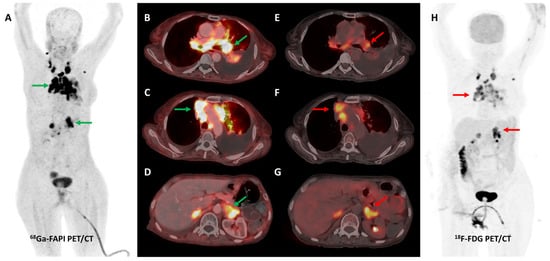

Several preclinical studies have demonstrated FAP expression in a vast majority (>90%) of ovarian cancers with negligible expression in normal ovarian tissue, benign and borderline tumors. FAP expression in epithelial ovarian cancers is associated with resistance to platinum-based chemotherapy, shorter time to recurrence, and overall worse clinical outcomes [113,114,115,116]. In a recent study, [68Ga]Ga-FAPI-04 showed negligible physiological accumulation in ovaries irrespective of the menstrual cycle phase, suggesting that it could overcome limitations associated with non-specific/benign ovarian FDG uptake [117]. Zheng et al. retrospectively compared [68Ga]Ga-FAPI-04 and FDG PET/CT in 21 patients with suspected (n = 11) or already diagnosed (n = 10) primary ovarian malignancy. FAPI was more sensitive than FDG PET/CT for the detection of primary tumors (100% vs. 78%), nodal metastases (100% vs. 80%), and peritoneal/pleural involvement (100% vs. 56%), leading to upstaging of disease in 19% (4/21) of the patients [118]. Figure 8 shows an example of FAPI PET/CT in a patient with ovarian malignancy.

Figure 8.

Forty-seven-year-old woman, a known case of ovarian carcinoma (clear cell type) post-surgery and adjuvant platin-based chemotherapy had rising serum CA-125 levels. She underwent [68Ga]Ga-FAPI-04 and FDG PET/CT for restaging, which revealed a heterogeneously enhancing lesion (~5.1 × 3.5 cm) in segment VII of the liver ((C,F)—green arrows) with intense FAPI uptake ((A,B,E)—green arrows) and no significant FDG uptake ((D,G,H)—red arrows) suggestive of liver metastasis.